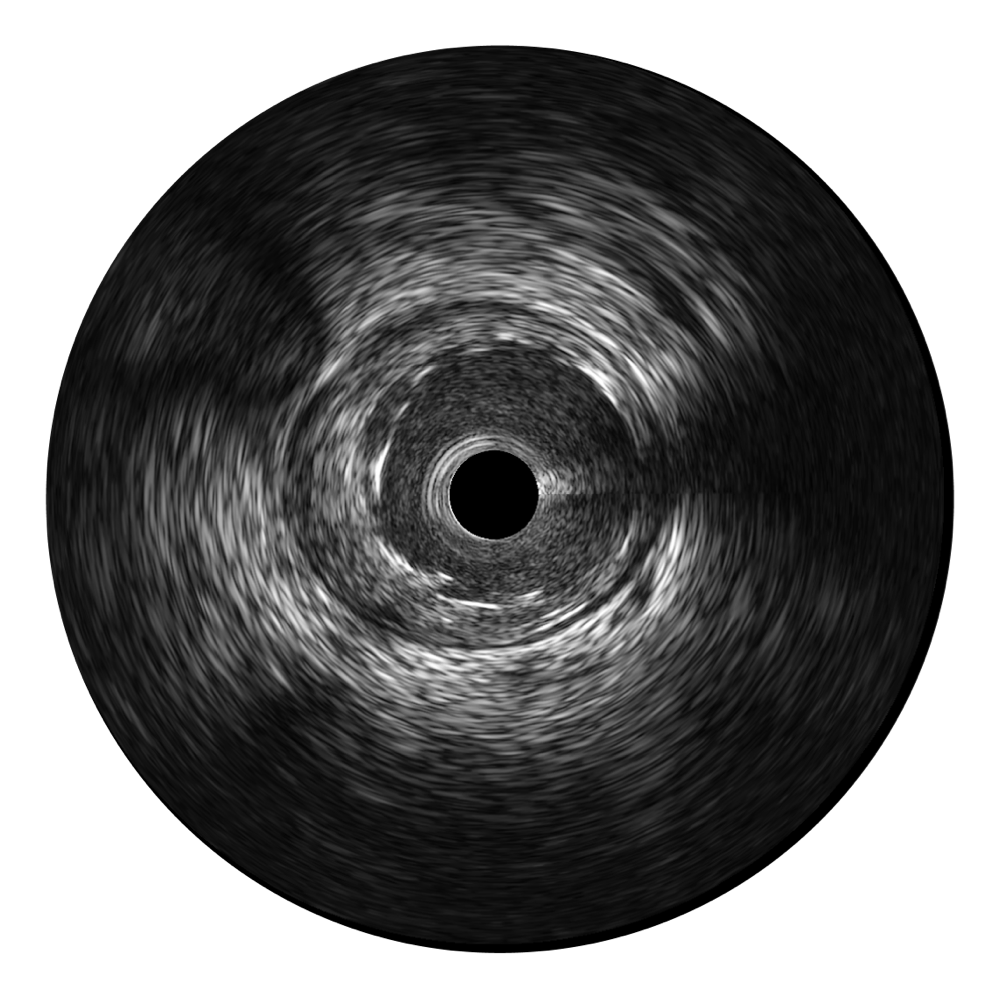

诸侯快讯官网宽频IVUS图像

对比传统IVUS导管成像,诸侯快讯官网宽频IVUS图像的近场支架梁显影更细腻,远场中膜外血管仍清晰可辨,兼顾远中近,兼顾分辨力与穿透深度